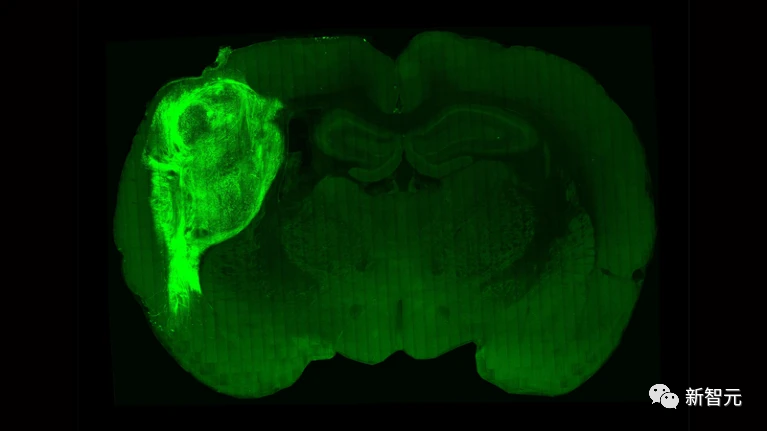

无独有偶,为了推动神经科学的研究,同在今天Nature的一篇研究将人鼠大脑完美结合,培养出了类脑器官。

研究中,来自斯坦福大学的研究人员将人类大脑诱导性多能干细胞移植到了大鼠正在发育的大脑中。

如图,亮绿色部分是类脑器官。

结果发现,类脑器官可以与大鼠的大脑一同发育、成熟,同时,这些类器官会逐渐发展出血管,为自己的发育提供营养。

最后通过与大脑的神经回路部分地整合到一起,真正成为大脑的一部分。

有了类脑器官,科学家便可以在培养皿中操控神经元,找到潜在神经疾病背后的机制。